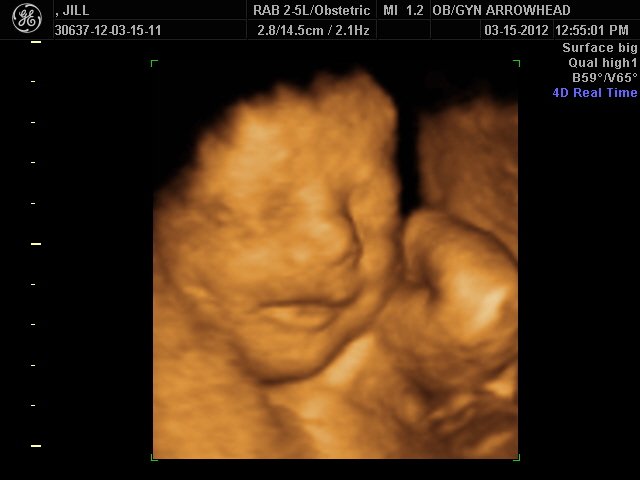

We offer complimentary 3D/4D Ultrasounds to all our OB patients around 30 weeks! The following photos are some examples of our work, shown with permission from our patients.